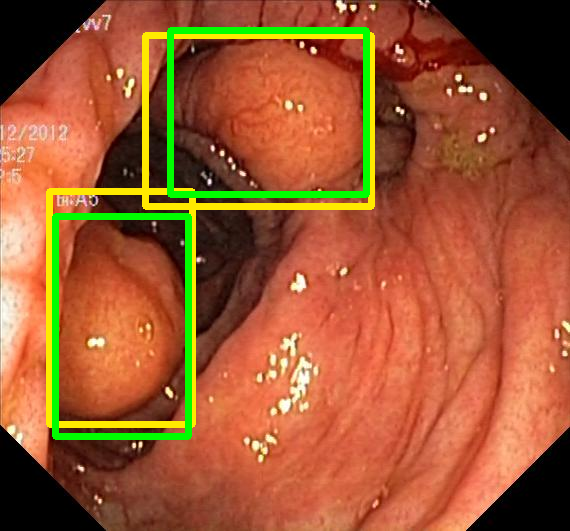

We evaluate the resulting object detection models using the test data, which is pre-processed in the same manner as the validation data, with AP@[.5:.95] (AP for conciseness), AP@.5 (AP5050{}_{50}start_FLOATSUBSCRIPT 50 end_FLOATSUBSCRIPT), and AP@.75 (AP7575{}_{75}start_FLOATSUBSCRIPT 75 end_FLOATSUBSCRIPT) computed for predicted bounded boxes with a confidence score \geq0.05. For all metrics, a higher value indicates better performance. The results are presented in Table VI, and some examples for predicted bounding boxes with a confidence score \geq0.5 are shown in Fig. 1.

RN-HK-MC RN-HK-BT RN-IN-MC RN-IN-BT RN-IN-SL RN-NA-NA Refer to caption Refer to caption Refer to caption Refer to caption Refer to caption Refer to caption Refer to caption Refer to caption Refer to caption Refer to caption Refer to caption Refer to caption VT-HK-MC VT-HK-MA VT-IN-MC VT-IN-MA VT-IN-SL VT-NA-NA Refer to caption Refer to caption Refer to caption Refer to caption Refer to caption Refer to caption Refer to caption Refer to caption Refer to caption Refer to caption Refer to caption Refer to caption

Figure 1: Targets (yellow bounding boxes) and predictions (green bounding boxes) for two randomly selected instances of the Kvasir-SEG test set. For conciseness, we denote ResNet50s with RN, ViT-Bs with VT, Hyperkvasir-unlabelled with HK, ImageNet-1k with IN, MoCo v3 with MC, Barlow Twins with BT, MAE with MA, supervised pretraining with SL, and no pretraining with NA-NA.